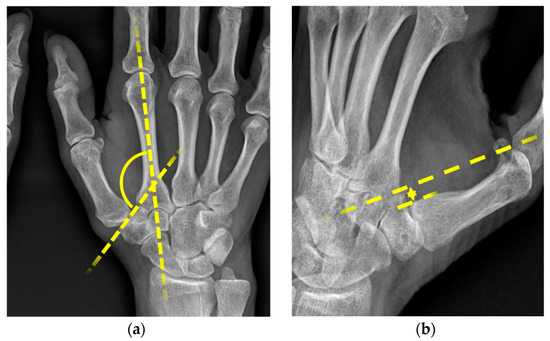

The absolute values for the slope angle defined by Kapandji 2002 [13] and for the bony offset of the os metacarpale I were determined. All measurements were performed by an experienced radiologist. The parameters collected for this study are displayed in Figure 1a,b.

Figure 1.

(a) Slope angle 1, (b) bony offset 2. 1 radiological measurement of slope angle in DP images, formed by the axis through the os metacarpale II and trapezium; 2 radiological measurements of width offset in zither player position (width between the lines along the ulnar edge of the trapezium and ulnar edge of the os metacarpale I).